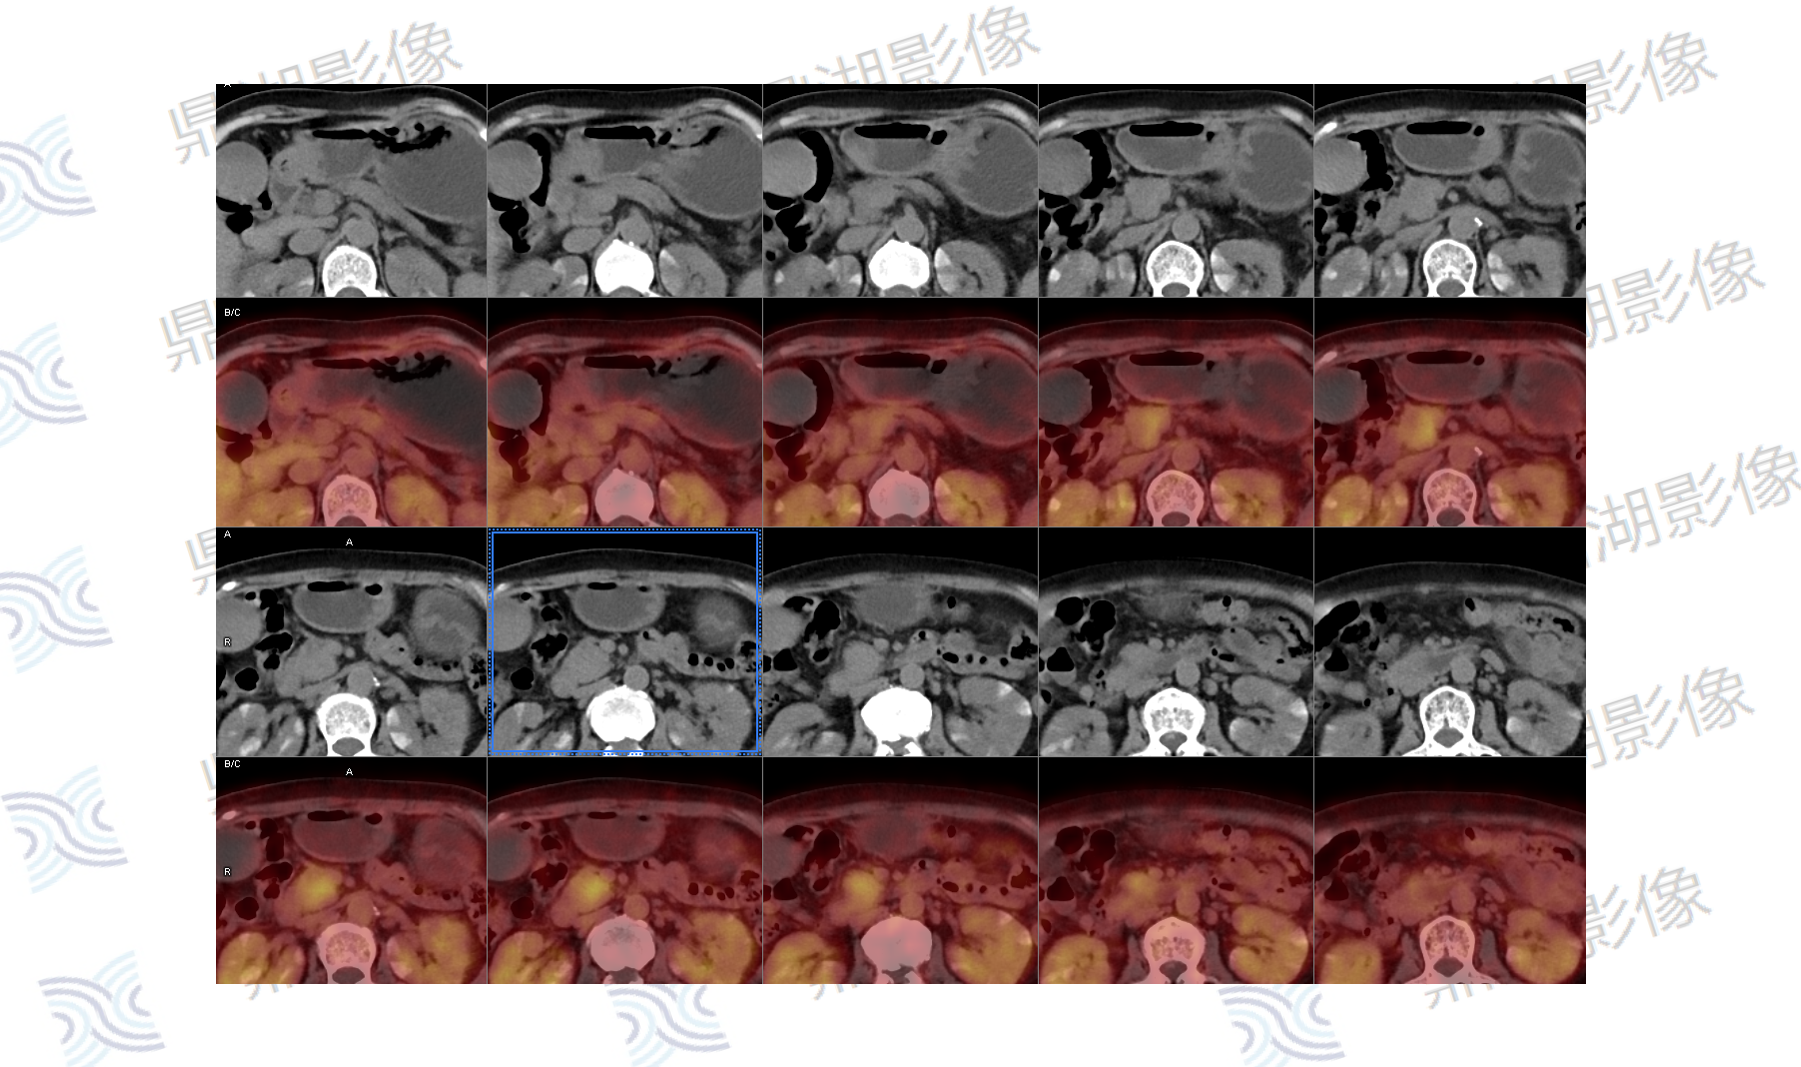

影像表现:胰腺钩突不规则软组织肿块,FDG摄取增高,SUVmax=4.3,病灶与邻近肠系膜上静脉分界不清,胰腺体尾部萎缩伴胰管扩张,胆总管及肝内胆管轻度扩张。